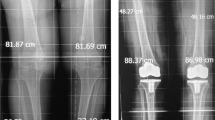

The morphologic differences identified among the ethnicities in this study indicated notable clinical implications on existing TKA design. For example, the AP of AMs (54.9 ± 4.4 mm) was similar to that of CFs (55.9 ± 3.3 mm), which could lead to the wrongful assumption of using sex-specific implants for AMs. However, a closer look reveals substantial ML and ML/AP ratio differences between these two groups, which could lead to underhang when using such implants for AMs. When comparing datasets with the same AP (57.4 mm), we found AMs (ML = 85.6 mm) had a 6-mm-larger ML than CFs (ML = 80 mm). Likewise, another comparison of datasets (AP = 49.7 mm) showed AMs (77 mm) had a 6-mm-larger ML than comparable CFs (ML = 71 mm).

In sizing the femoral component, the AP is important in maintaining the flexion-extension gap, optimizing patellofemoral tracking and tension in the quadriceps mechanism; all of which impact knee motion and stability. In contrast, the ML determines bone coverage and soft tissue tension. Current implant designs and surgical techniques account for morphologic differences by compromises during surgery to fit the average implant on the measured anatomy, avoiding overhang and soft tissue impingement with a larger prosthesis or instability with a smaller prosthesis.

New anatomic and morphologic insights for both the femur (Fig. 11) and tibia (Fig. 12) brought forth in this paper may help foster implant design changes in all component parts in TKA; however, further evaluation is needed to determine whether these design changes would improve clinical outcome. Ethnic differences in the anatomy of the knee have also been identified by this study. Some Asian surgeons claim current knee implants do not fulfill the requirements of their patient population [21]. Further investigation is needed to evaluate any clinical impact of implant designs based on these ethnic differences.